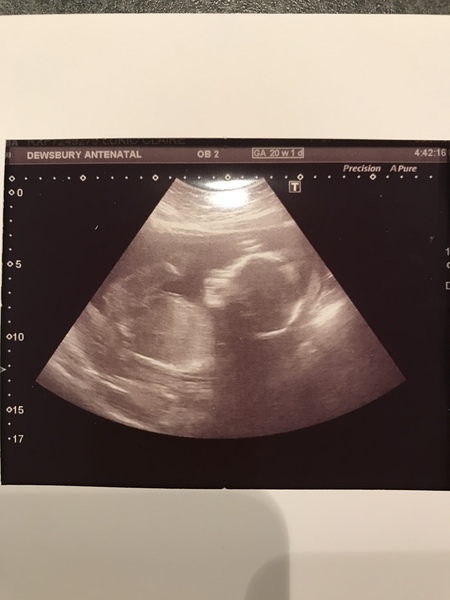

Still no movements yet at 20+6

Low, anterior placenta so I'm trying not to be concerned about it, because baby was really wriggly on the scan, and all measurements etc were perfect, but I'd like some reassurance please!